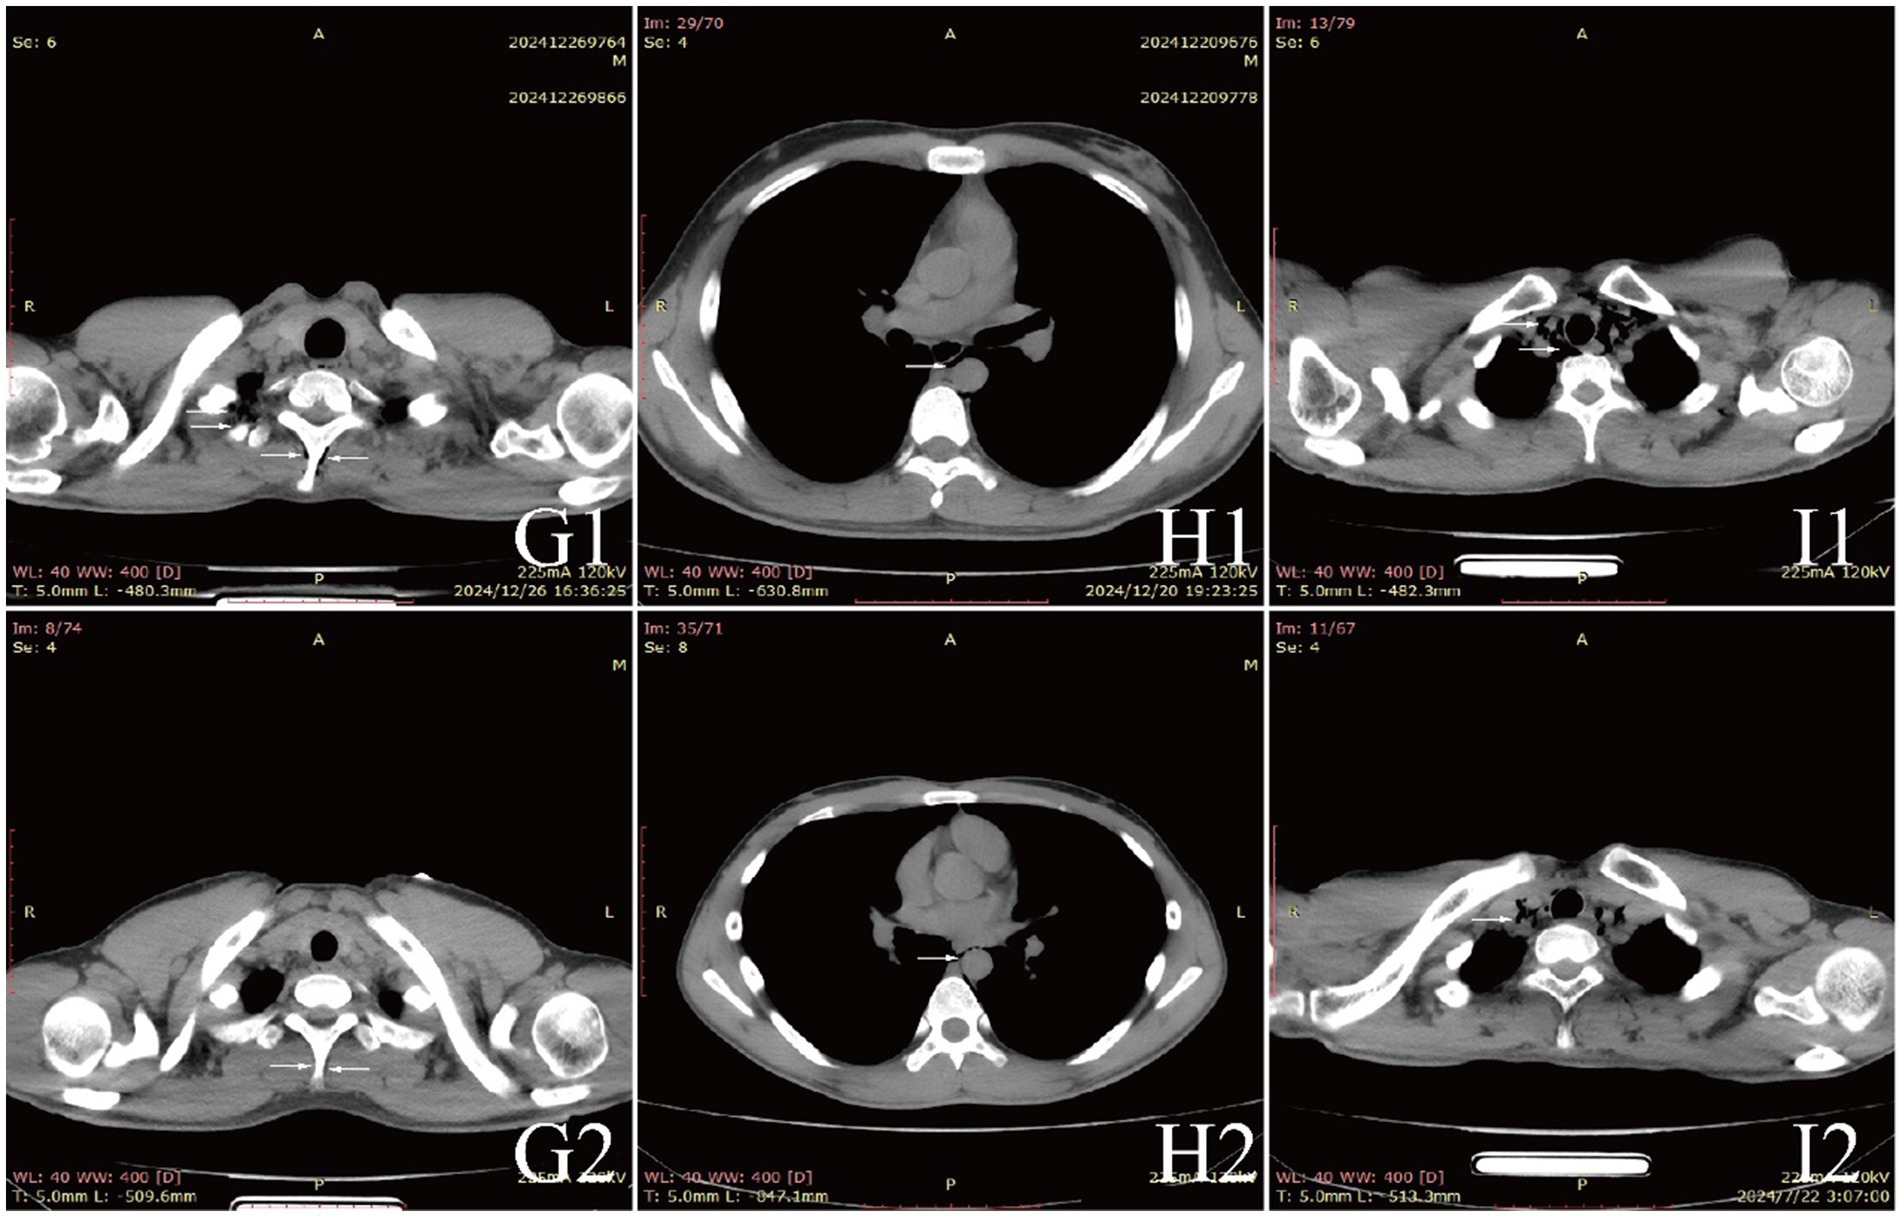

Examinations affected by the hypoxic environment of high altitudes, all patients exhibited varying degrees of increased red blood cell count, hemoglobin concentration, and uric acid (UA). Case 6 and 7, who were diagnosed with acute appendicitis and pulmonary infection, respectively, showed increased percentages of neutrophils. Case 1, in the acute phase of aortic dissection, also had an elevated white blood cell count. Additionally, we observed that D-dimer in the blood is a good indicator of myocardial or vascular damage. It showed varying degrees of elevation in patients with aortic dissection, while this indicator remained normal in other patients, maintaining a high negative predictive value. It is noteworthy that the serum potassium (K+) levels of all patients were high, with five patients having levels above the normal range. The average serum K+ level for all patients was 5.39 ± 0.73 mmol/L, this may be due to the increased metabolism in high altitude areas (Table 3). The diagnosis of extra-pulmonary emphysema for all patients was confirmed through CT examination. Case 1, 2, 3, 6, and 7 showed subcutaneous emphysema, while the others showed mediastinal emphysema. Specific imaging manifestations are shown in Figure 1.

Figure 3. CT comparison images of extra-pulmonary emphysema treatment before and after for Case 7 to Case 9.

All patients were diagnosed with extra-pulmonary emphysema through CT scans, which showed gas infiltration in the mediastinum or subcutaneous tissue. The patient with aortic dissection was urgently transferred to a lower altitude area for “aortic arch artificial vessel replacement surgery.” Case 6 underwent “appendectomy” for treatment, and three patients received antibiotic therapy. All patients were given symptomatic and supportive treatment, including oxygen therapy. Six were given oxygen via a face mask, two received a nasal cannula, and one was assisted with non-invasive ventilation. In addition to case 1, they also received hyperbaric oxygen therapy at 2.0 ATA. Follow-up showed that all patients responded well to the treatment, their conditions improved, and the emphysema was largely absorbed (Figures 1–3).